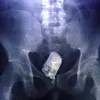

Dari Botol Hingga Pistol, 8 Benda Ini Pernah Ada di Tubuh Manusia

Simak beberapa cerita kumpulan benda yang pernah ada di tubuh manusia. Lihat list-nya di sini.